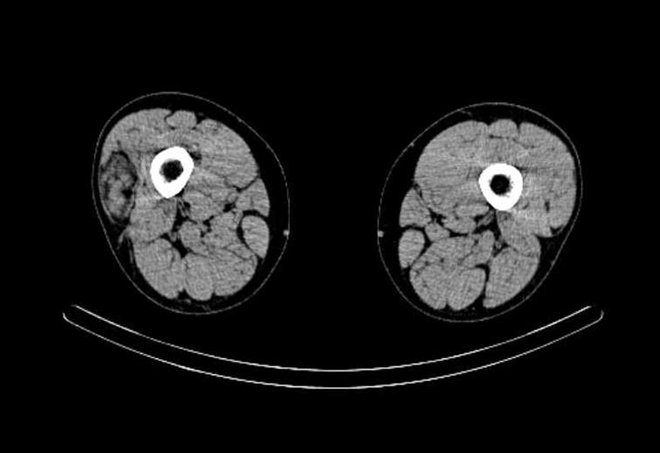

/ Obr. č. 5: „low dose“ CT obou stehen – transverzální řez.

/ Obr. č. 6: „low dose“ CT obou stehen – transverzální řez.

/ Obr. č. 7: „low dose“ CT obou stehen – transverzální řez.

/ Obr. č. 8: „low dose“ CT obou stehen – transverzální řez.

/ Obr. č. 9: „low dose“ CT obou stehen – transverzální řez.

/ Obr. č. 10: „low dose“ CT obou stehen – transverzální řez.

Pozorujeme asymetrickou perfuzi se zvýšenou perfuzí v ložisku v laterální části pravého stehna, přičemž perfuze je nejvíce zvýšená na počátku vyšetření, pak se intenzita této hyperperfuze o něco snižuje. V pozdní kostní fázi je vyšší depozice radioaktivity v ložisku ve ventrální části diafýzy pravé kosti stehenní subperiostálně (ve stejné úrovni jako ložisko v laterální části stehna, ale obě ložiska se nekryjí), drobné ložisko v pravé části obratle L5. Výrazný nález je při vyšetření „low dose“ CT, který odpovídá popisovanému nálezu na CT. Závěr: drobné ložisko se zvýšenou osteoblastickou aktivitou v pravé části obratle L5 při lehkých degenerativních změnách. Patologické ložisko se zvýšenou perfuzí v laterální části pravého stehna, ložisko se zvýšenou osteoblastickou aktivitou ve ventrální části diafýzy pravé stehenní kosti subperiostálně (obě popsaná ložiska jsou ve stejné úrovni stehna, ale svou lokalizací se nekryjí). Při vyšetření pomocí „low dose“ CT bohatě vaskularizované ložisko nepravidelného tvaru v laterální části pravého stehna zasahující až ke stehenní kosti.